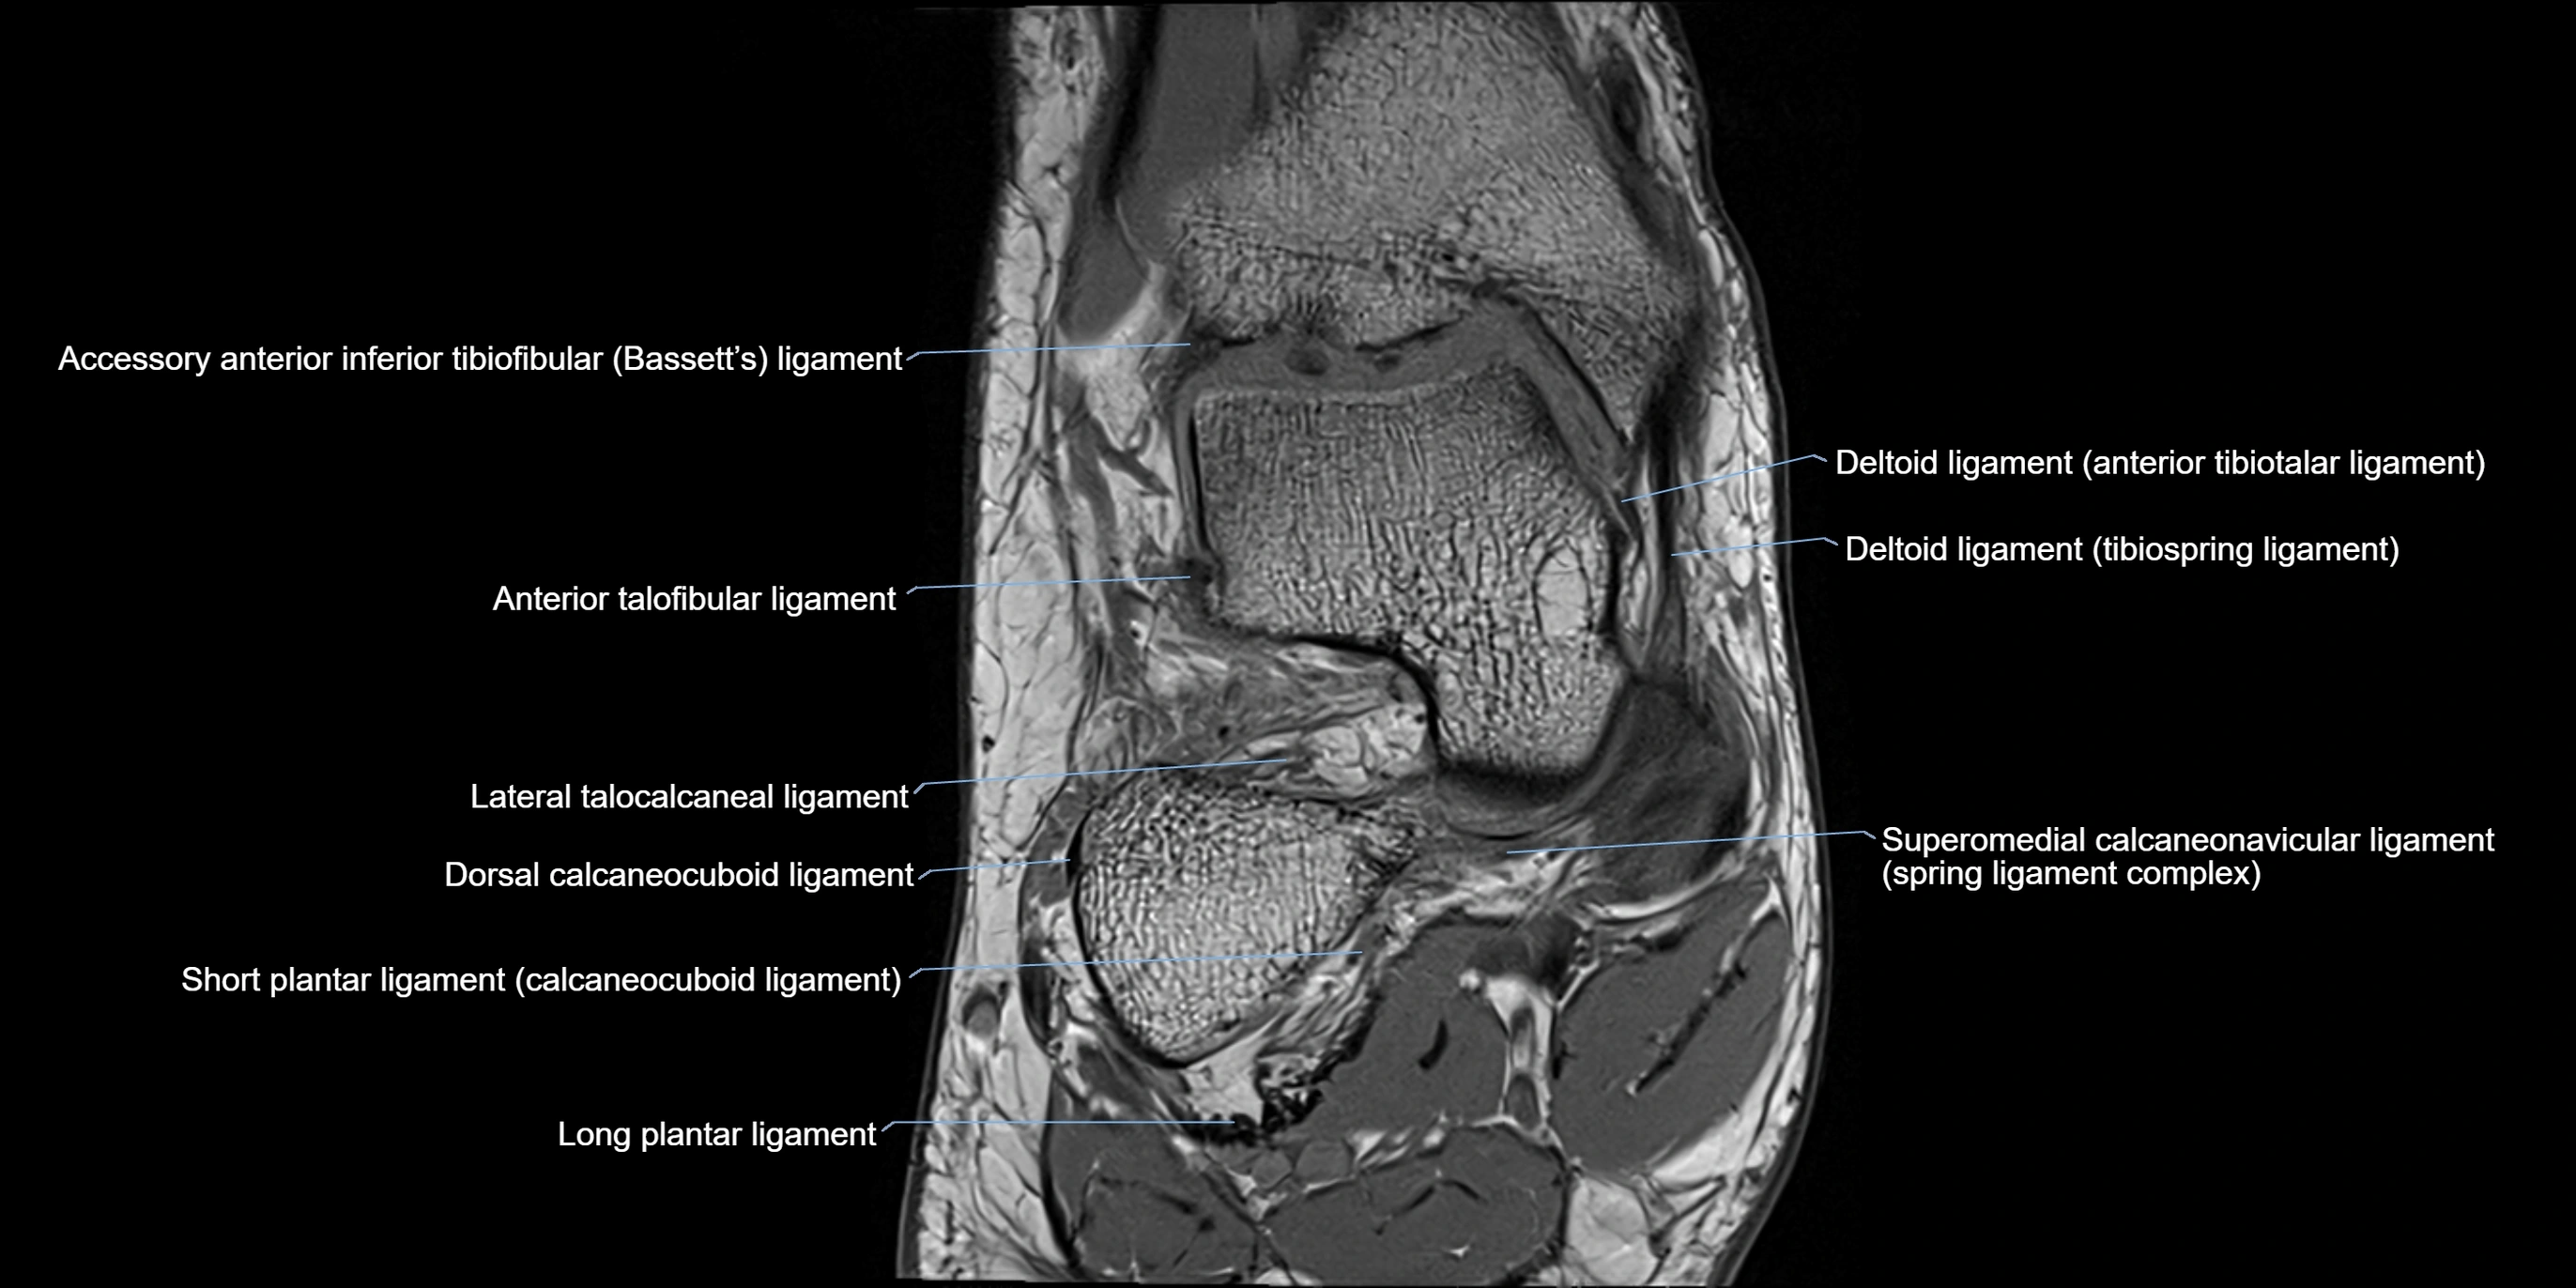

MRI image

image